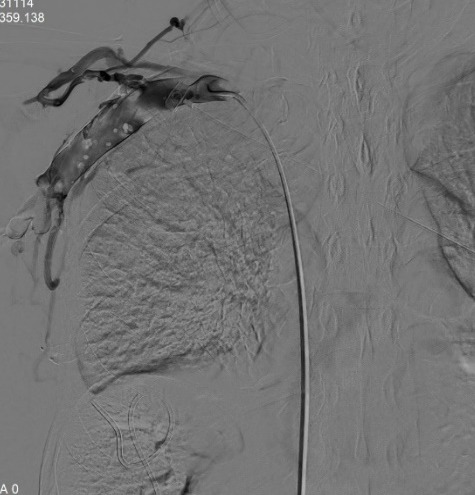

術(shù)前

患者既往有中心靜脈導(dǎo)管置入史,住院期間患者發(fā)現(xiàn)右上肢腫脹,范圍累及整個右上肢,腫脹程度逐漸加重,皮膚張力增高。右上肢靜脈超聲提示:右側(cè)鎖骨下靜脈血栓形成。遂后經(jīng)我院介入科會診并行右上肢靜脈及中心靜脈造影示:右側(cè)鎖骨下靜脈近心端及頭臂靜脈明顯閉塞,右側(cè)鎖骨下靜脈遠心端繼發(fā)血栓形成。

完善各項術(shù)前評估和準備后,介入科韋運豪主治醫(yī)師、熊偉主治醫(yī)師、朱海副主任醫(yī)師及李衡住院醫(yī)師等對患者進行上述手術(shù)方案的操作。術(shù)中將導(dǎo)管成功通過閉塞段血管,再次造影明確閉塞段長度、寬度及鎖骨下靜脈遠心端血栓情況。

經(jīng)過測量確定優(yōu)先使用球囊進行狹窄段靜脈預(yù)擴張,在韋運豪主治醫(yī)師、熊偉主治醫(yī)師及朱海副主任醫(yī)師的合作下對閉塞段血管反復(fù)擴張數(shù)次,再次造影見閉塞段血管較前改善,但靶血管區(qū)狹窄程度仍約80%,根據(jù)國內(nèi)外專家指南共識,當經(jīng)皮腔內(nèi)血管成形術(shù)(PTA)后閉塞血管段發(fā)生彈性回縮或殘余狹窄>30%時,具有進一步行支架置入術(shù)干預(yù)的指征。